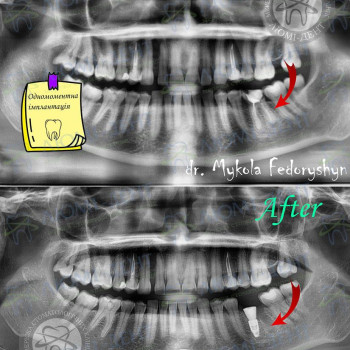

Довго не могла наважитися на імплантацію, тому що здавалося, що це складне і довге лікування. У Люмі-Дент на Позняках потрапила до Федоришина Миколи Анатолійовича і вже......

| ✅ Стоматолог-хирург Николай Анатольевич Федоришин | 470 грн |